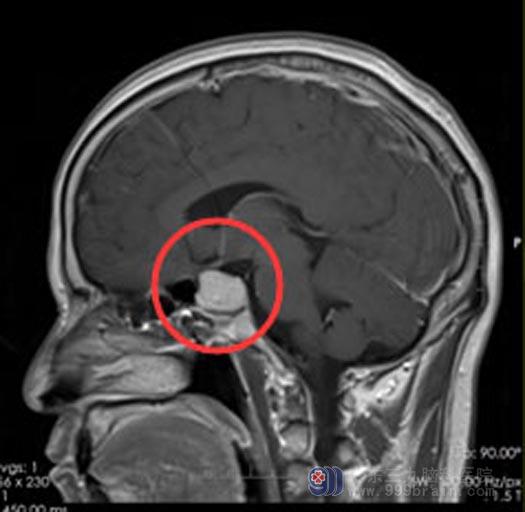

徐先生七年前视力下降、经常头痛,在全麻下行鞍区垂体瘤切除术。出院后一直没有进行术后复查,近期出现头痛、恶心,他以为是普通的感冒症状,并未在意。症状一直没有缓解,在广东三九脑科医院头颅核磁共振检查提示: “鞍内病变,考虑肿瘤残留或复发,合并瘤卒中”。

手术前